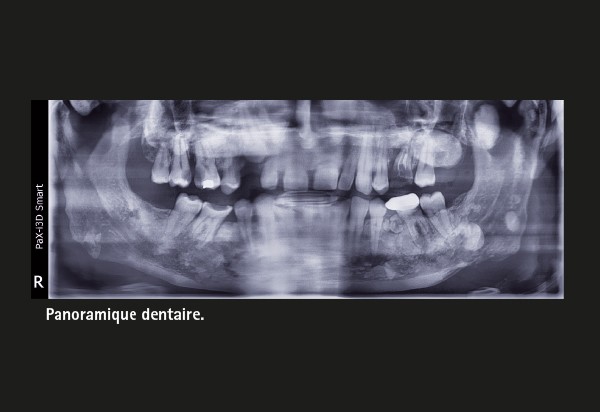

Tony D, 37 ans, est adressé par son chirurgien-dentiste traitant pour avis sur des lésions ostéo-condensantes multiples des maxillaires découvertes fortuitement au détour d’une radiographie panoramique de routine.

L’examen clinique met en évidence une volumineuse tuméfaction de l’hémi-palais dur gauche, indolore et recouvert d’une muqueuse normale.

On retrouve à la radiographie une canine incluse, deux volumineuses lésions radiodenses ovalaires bien délimitées et ceinturées d’un liseré radioclaire localisées à l’hémi-maxillaire gauche et de multiples lésions radio-opaques.